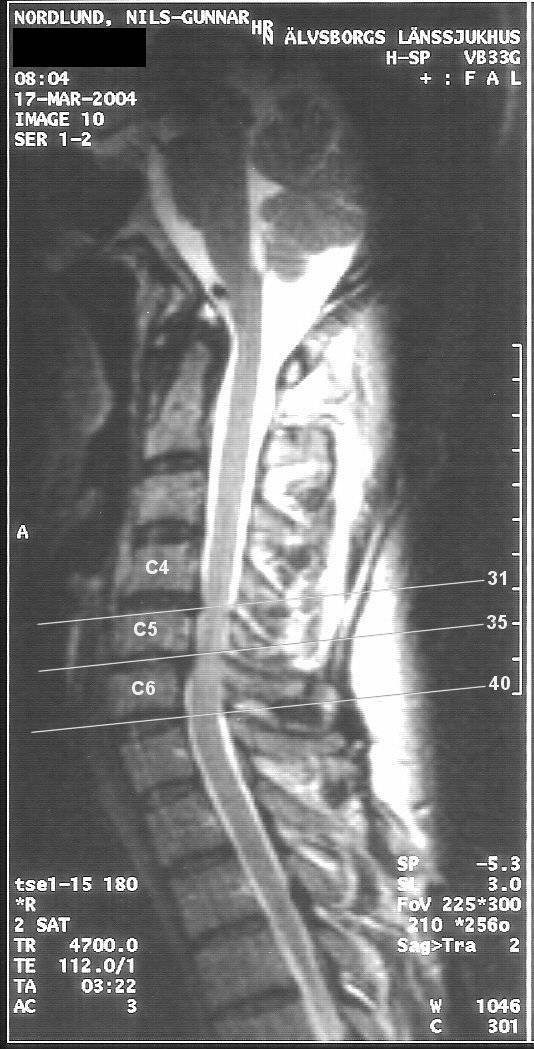

Jag bifogar även ett antal, av mig digitaliserade bilder från MR, 2004-03-17;

Bild 10, (tvärsnitt)